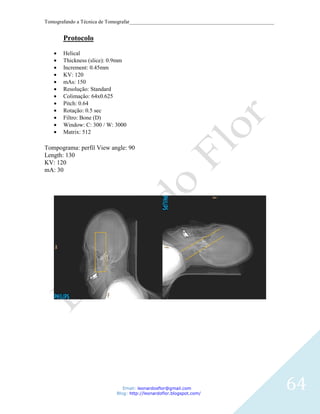

Protocolo

Helical

Thickness (slice): 0.9mm

Increment: 0.45mm

KV: 120

mAs: 150

Resolução: Standard

Colimação: 64x0.625

Pitch: 0.64

Rotação: 0.5 sec

Filtro: Bone (D)

Window: C: 300 / W: 3000

Matrix: 512

Tompograma: perfil View angle: 90

Length: 130

mA: 30

Obs: o exame e realizado de duas etapas boca aberta e boca fechada.